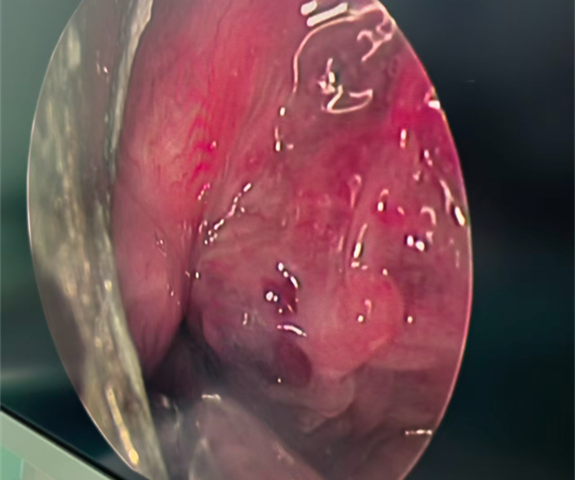

手术顺利进行,按照提前制定好的手术计划,在四方开口器辅助下,支撑喉镜暴露了下咽部梨状窝肿物。手术团队采用403低温等离子刀头先将肿瘤的滋养血管凝固栓塞,然后在高清视野下距瘤体边缘3mm处凝切并细致分离瘤体,在不损伤气道、喉部杓状软骨、室带、声带、食管黏膜的情况下将肿瘤顺利完整切除。术中尽量保留了瘤体边缘的健康黏膜。手术仅用时半小时,出血不足10ml,术后留置胃管以预防感染及出血。

图片

经过医护团队的精心护理,李伯伯术后5天顺利出院,呼吸、吞咽、发音功能均恢复正常。此次手术不仅是我院首例,更是湖南省县级医院首例梨状窝低温等离子血管瘤切除术。